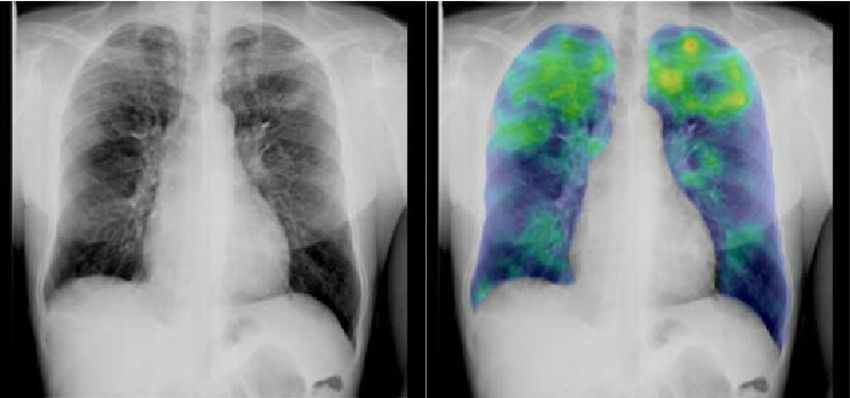

判断发展中国家的结核病情况

识别图像中的模式(Pattern)是现有人工智能系统中最强有力的一点,研究人员现在正在训练人工智能检查胸部x光片,识别结核病。这项技术可以为缺乏放射学家的结核病流行地区带来有效的筛查和评估手段。

用于检测和诊断癌症的传统方法包括计算机断层扫描( CT )、磁共振成像( MRI )、超声和X射线。不幸的是,许多癌症无法通过这些技术得到足够准确的诊断,从而可靠地挽救生命。微阵列基因图谱的分析是一种替代方法,但这项技术需要计算很多小时,除非这项技术可以使用AI替换。现在已经被证明,斯坦福大学的人工智能诊断算法与由21名经委员会认证的皮肤科医生的团队一样有效地从图像中检测潜在的皮肤癌。Startup Enlitic正在使用深度学习来检测CT图像中的肺癌结节,其算法比作为一个团队工作的专家胸科医生的准确率高50%。